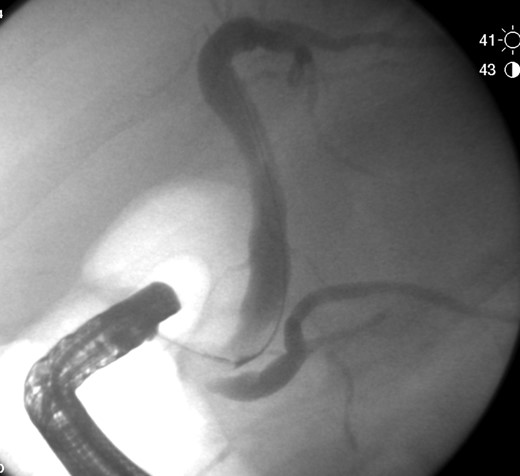

The patient was admitted for management of obstructive jaundice with possible cholecystitis. On hospital day 1 his bilirubin increased to 5.1, he was given Vitamin K and fresh frozen plasma to correct his coagulopathy and he was taken for endoscopic retrograde cholangiopancreatography (ERCP). During ERCP, the common bile duct (CBD) was cannulated and swept revealing a moderate amount of maroon clot (Fig. 2). No other debris or stones were noted to be within the CBD on final fluoroscopic image (Fig. 3).

Endoscopic image of ERCP with hemorrhagic contents being removed.